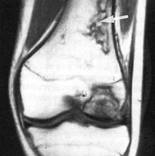

Infarct metafizar cu osteonecroza decondil medial - LES - T1

EXPLORAREA PRIN REZONANTA MAGNETICA A GENUNCHIULUI

IRM permite:

studiul mutiplanar al suprafetelor complexe ale genunchiului

obtinerea de imagini cu un bun contrast intre diferitele structuri anatomice

confirmarea diagnosticului clinic

pune indicatia de artroscopie

Indicatii:

patologia osteo-articulara: tumori, infectii, sinovite vilo-nodulare, osteocondromatoza.

Meniscurilor

explorarea chisturilor articulare sau periarticulare

necroze condiliene